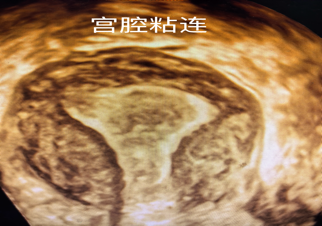

宫腔粘连是由于子宫内膜基底层受损,导致子宫内膜纤维化。粘连可能形成纤维组织带、宫腔内瘢痕,使宫腔变形甚至闭锁。

想象一下,子宫腔就像一个房间,里面原本光滑柔软的“墙壁”(子宫内膜)受了伤。伤口愈合时,不像原来那样平整,反而像长了“疤”(纤维化)。这些“疤”可能会让子宫腔的“墙壁”和“墙壁”之间粘在一起(形成粘连带),甚至把房间的一部分或整个都“堵死”(变形或闭锁),空间就变小了、不规整了。

宫腔镜筛查

诊断金标准

可直接观察粘连范围及程度